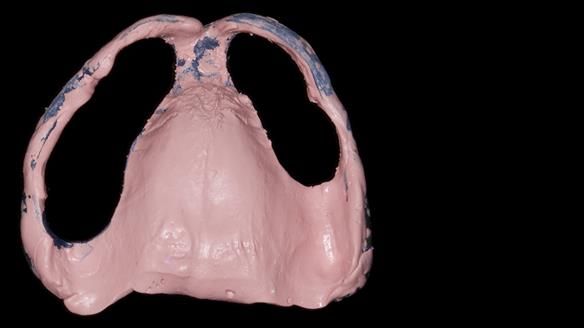

We provided her with an immediate upper denture (Mk 1), followed by a definitive metal-based upper denture (Mk 2). A lower removable partial denture was discussed, to be made only if needed once the upper treatment was complete. However, at review, this wasn’t necessary — Adnana had excellent neuromuscular control and function, even with a shortened dental arch (SDA).

Rowan, Sam Hesketh and Chris Hesketh provided the stunning technical work. I am very lucky to have them.